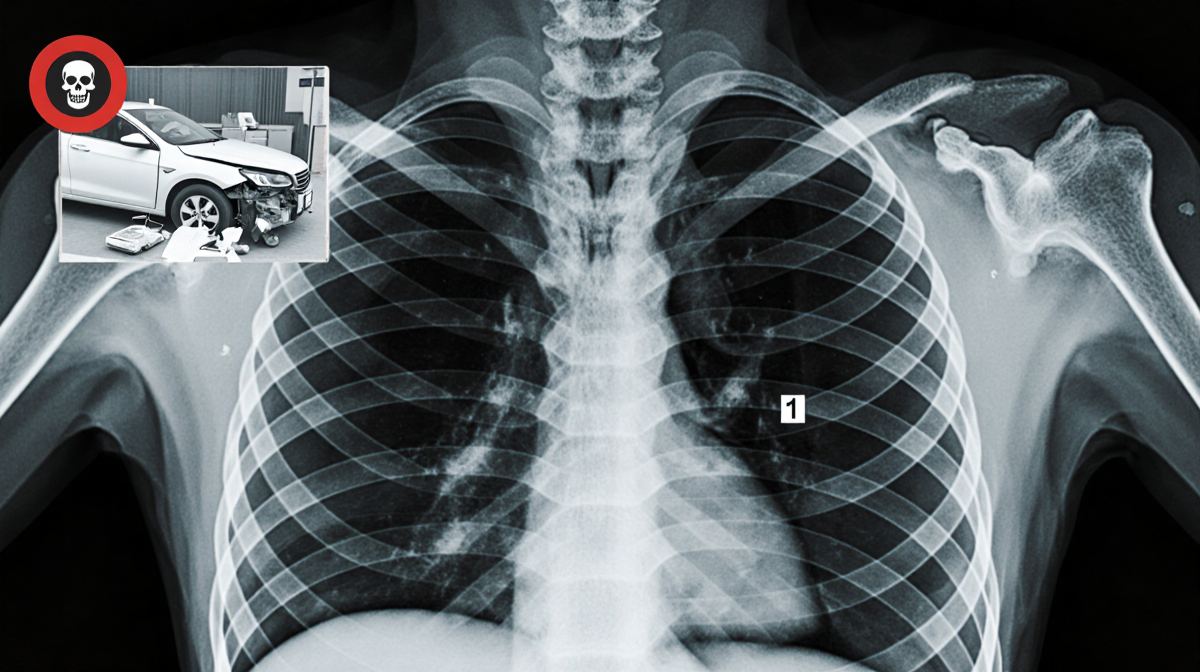

The post included images of bruising and cuts on his forehead, a thumbs-up in a hospital bed, and X-ray photos with arrows pointing to each break. Fans responded with well-wishes in the comments.